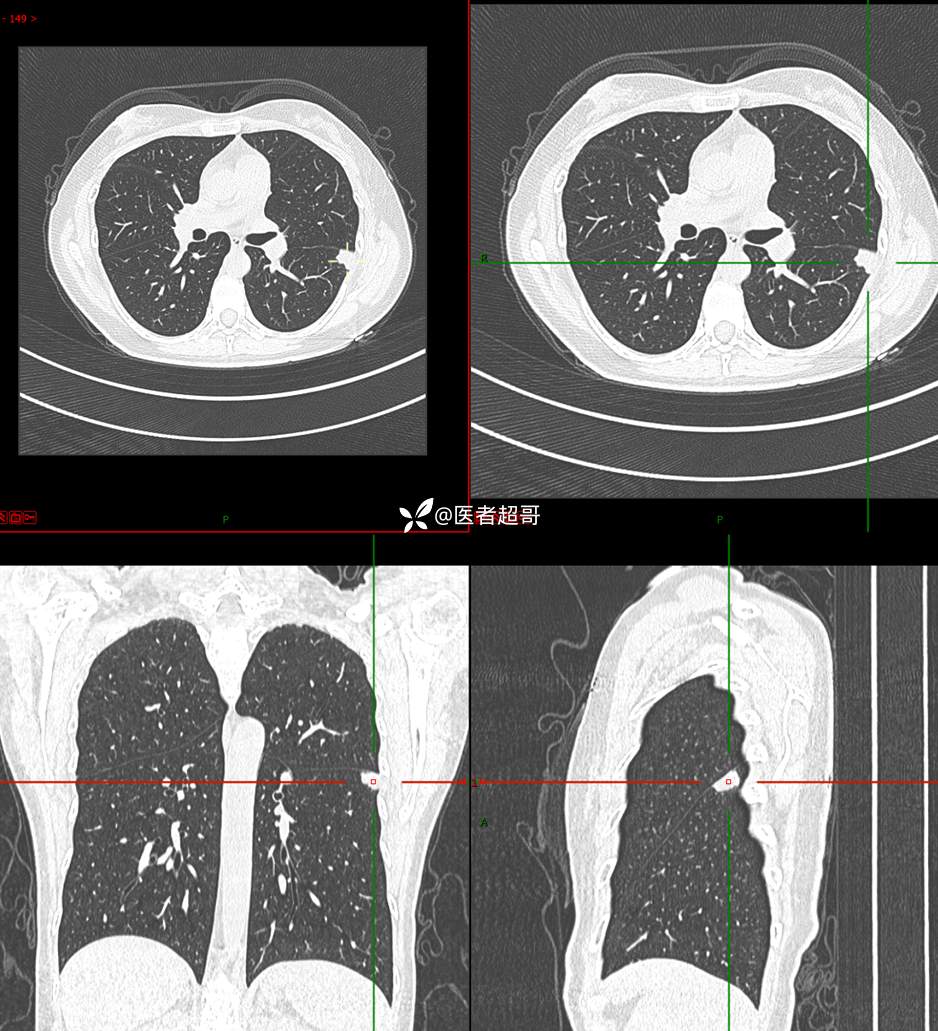

【影诊笔记705】查体发现肺肿物2月余,请诊断分析~~~

主 诉:查体发现肺肿物2月余

现病史:患者于2月余前行X线及胸部CT示:左肺结节。当时患者无明显不适,行抗炎治疗后复诊。于我院查胸部(肺)CT平扫示:左肺下叶实性小结节,请结合临床及原片,必要时进一步检查;双肺钙化灶右肺上叶微结节,建议随诊肝内钙化灶,门诊以“肺肿物”收入院。患者自发病以来,咳嗽咳痰,无痰中带血,无咯血,无胸闷胸痛,无心慌气短,无发热盗汗、无全身乏力,无头痛头晕,无恶心呕吐,无腹痛腹胀,无声音嘶哑及呛咳。患者自发病以来,神志清,精神可,饮食可,睡眠良好,大小便正常,近期体重未见明显增减。